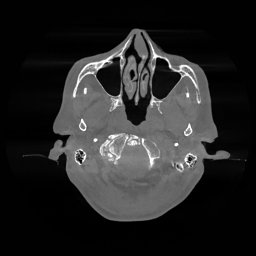

III-D Real Clinical Data Experiment

The experimental results on clinical head data are shown in Fig. 4. The reference images were reconstructed using the fast iterative shrinkage-thresholding algorithm (FISTA) with total variation regularization from non-truncated projection data. In the WCE reconstructions (Fig. 4(b)), severe truncation prevents accurate recovery of anatomical structures outside the FOV. Despite being trained solely on simulated data with a domain gap, all deep learning models can restore a substantial portion of the missing anatomy. Among them, the diffusion-based methods recover soft-tissue boundaries more faithfully than the conventional deep learning approach FBPConvNet, highlighting their stronger image generation capability. However, cDDPM reconstructions exhibit more noticeable noise than those from other methods, consistent with the simulated data results. The patchDiffusion model introduces artifacts within the FOV, likely due to its patch-wise processing strategy. While I2SB shares the same limitations as other diffusion models in perfectly restoring soft-tissue detail, it produces fewer residual noise patterns and fewer artifacts within the FOV boundaries. Overall, Fig. 4 demonstrates the strong efficacy of I2SB in reconstructing real CBCT data.